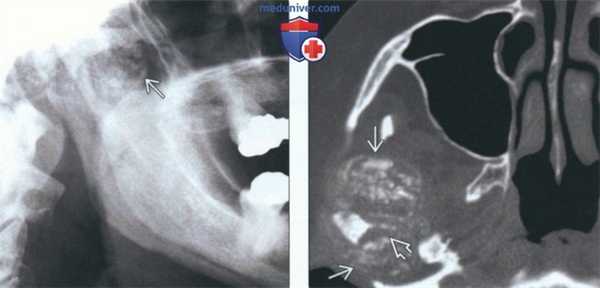

(Слева) На рентгенограмме нижней челюсти в боковой проекции визуализируется крупное объемное образование с диффузным обызвествлением, представляющее собой отложения КПФД в ВНЧС. Из-за наложения сторон невозможно сказать точно, где находится образование - справа или слева.

(Справа) На аксиальной КТ в костном окне у этою же пациента можно оценить размеры хорошо отграниченного объемного образования спереди и сзади от мыщелка. С внутренней стороны мыщелка визуализируется крупный рентгенонегативный дефект (эрозия).

(Слева) На сагиттальной реформатированной КЛКТ левого ВНЧС у пациента с болезнью накопления КПФД визуализируются большие рентгеноконтрастные образования в суставном пространстве наряду с эрозиями мыщелка и суставной ямки и склерозом.

(Справа) На корональной реформатированной КЛКТ у этого же пациента визуализируются меньшие обызвествленные образования снаружи, изнутри, сверху от мыщелка. Обратите внимание на обширные эрозии суставной поверхности мыщелка и внутренних отделов суставной ямки. Картина имитирует хондросаркому.